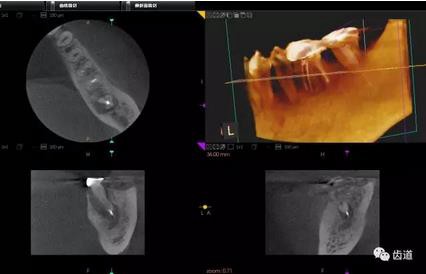

2、下頜磨牙阻生

下頜第二第三磨牙阻生口腔曲面斷層片影像

下頜第二第三磨牙阻生CBCT影像定位

三種圖片的影像學(xué)比較